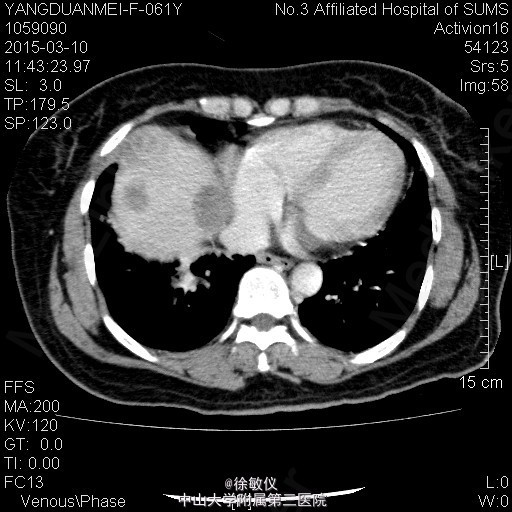

老年女性,主诉:咳嗽2月,胸部CT发现中央型肺癌1天。 现病史:患者2月前无明显诱因出现咳嗽伴胸闷气促,伴少量白色粘液痰,无痰中带血、咯血等不适,当时自行服用“消炎药”治疗(具体不详),2月来症状逐渐加重,至当地医院就诊,查胸部CT提示:右侧中央型肺癌并纵隔淋巴结转移,肝脏考虑转移灶。现为求进一步治疗入院。近期体重减轻2斤。 查体:生命体征平稳,全身浅表淋巴结未扪及肿大。心肺腹查体无特殊。 胸部CT:1、右下中央型肺癌,并右肺门及纵隔多发淋巴结转移;右中间段支气管、中下叶支气管狭窄、闭塞,右肺阻塞性炎症,考虑右侧肺动脉、右下肺静脉受侵。2、肝S4、S8转移瘤。 诊断: 右侧中央型肺癌并肝转移。